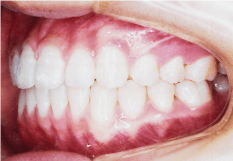

- 子どもの矯正(小児矯正)は、あごの骨のバランスや大きさを整える「1期治療(骨格矯正)」と、永久歯が生えそろってから歯の位置を整える「2期治療(歯列矯正)」の2段階からなります。

第1期治療

乳歯と永久歯が混じった時期の治療で、主に成長を利用した治療を行ないます。

(6~10歳)

第2期治療

歯の1本1本に装置をつけ、歯の根までコントロールして最終的な咬み合わせを作ります。